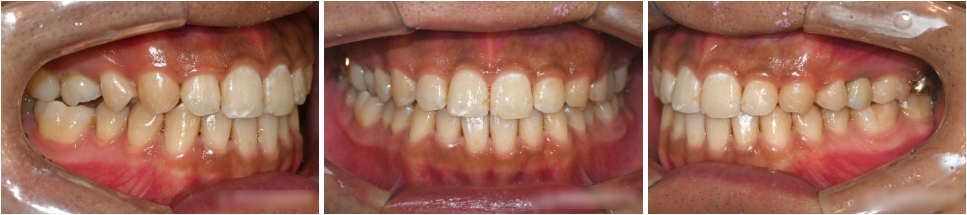

『치료 후』

부분교정과 임플란트 수술을 마친 후 모습입니다.

치아를 이동시켜 공간을 만드는

부분교정은 비교적 빠르게 마무리되었습니다.

그와 동시에 앞니도 가지런히 배열 완료되었습니다.

처음엔 좁았던 발치 공간이

제대로 확보되면서

지르코니아 보철(크라운)이 계획대로

예쁘게 잘 들어간 모습입니다.